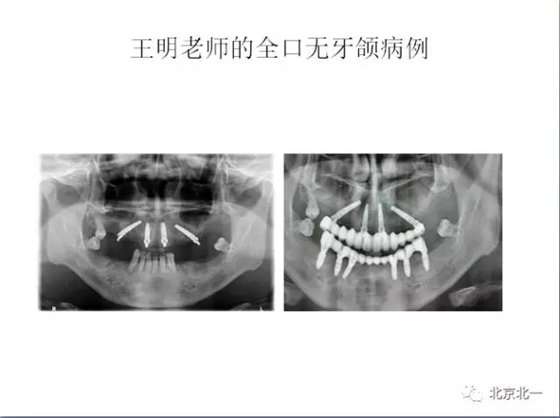

王明

北一種植聯(lián)盟首席專家;

擅長:種植外科,尤其專長復(fù)雜牙種植,自體骨移植同期種植,上頜竇底內(nèi)外提升同期種植技術(shù),美學(xué)區(qū)種植技術(shù),即刻種植外科與即刻負(fù)重技術(shù),軟組織成形外科種植技術(shù)及全口無牙頜ALL-ON-FOUR技術(shù),種植并發(fā)癥和種植急癥處置等手術(shù)治療,從事口腔頜面外科,正頜外科、頜面部整形、微創(chuàng)拔牙,笑氣無痛舒適種植十余年。